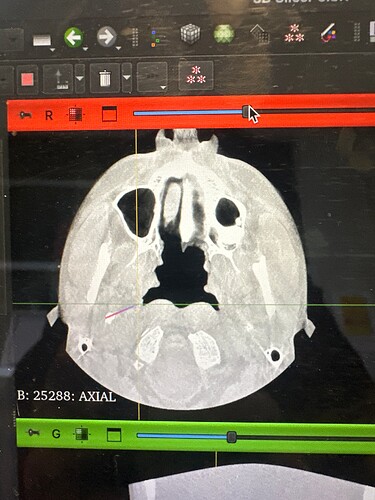

I was diagnosed yesterday by an oral surgeon after a CT scan. I’ve attached them for y’all’s thoughts.

Anyways, let me know what you think of the scans. They did not show my blood flow, just the bone structures.

Wow @Girgz they are some serious spikes! I am sure there will be more comments about these from other members soon. I wish you luck with getting these sorted.

Wow, they re very nasty styloids! They are pretty long, very pointy & angled…they’re very weird looking at the top, they look quite thick there, & then jointed- this often happens when the stylo-hyoid ligament calcifies at the end of the styloid, or very rarely if there’s been a fracture. It looks like you have quite a big gape between the styloids and the C1 processes because of their angle, which is good as often there can be compression of the internal jugular veins between the two.

It looks like you’re most likely clear of IJV issues, but ICA could be a problem w/ as long as your styloids are. Without being able to see the ICAs in relation to your styloids, there’s no way to tell for sure. Dr. Hackman could certainly help with that. Dr. Fargen is booked out for months so Dr. Hackman would be a better place to start, plus, I don’t know if Dr. Fargen does many ES surgeries & Dr. Hackman is very experienced w/ them.